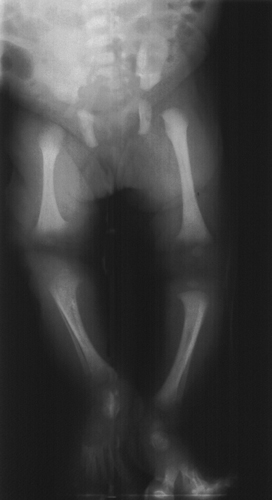

γλουτό και στο αριστερό κάτω άκρο. Η λεπτομερής κλινική εξέταση και η απλή ακτινογραφία

αποκάλυψαν ελαφρά ανισομέλεια (εικόνα 5), χωρίς δομικές ανωμαλίες των οστών.

Το μήκος του δεξιού ποδιού ήταν 22εκ και του αριστερού 20εκ (ο δεξιός μηρός

ήταν 2εκ μακρύτερος από τον αριστερό, 11εκ και 9εκ αντίστοιχα). Η εξέταση με

Εικόνα 5. Απλή ακτινογραφία

που δείχνει ελαφρά ανισομέλεια, χωρίς δομικές ανωμαλίες των οστών.